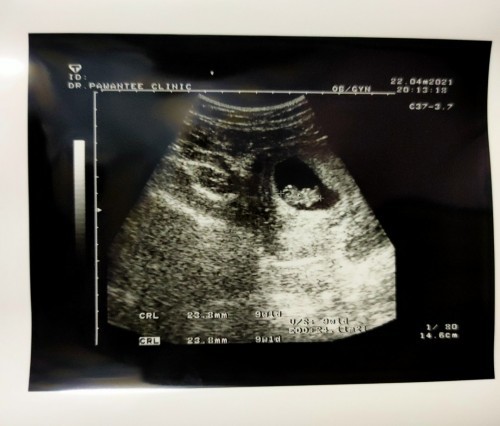

รอลุ้นอยู่ค่ะ..น้อง 9 สัปดาห์